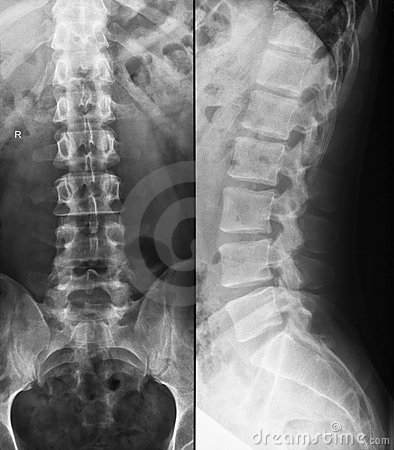

Ankylosing spondylitis

Note: normally, anterior margin of the vertebral body should be concave! Note the image below!